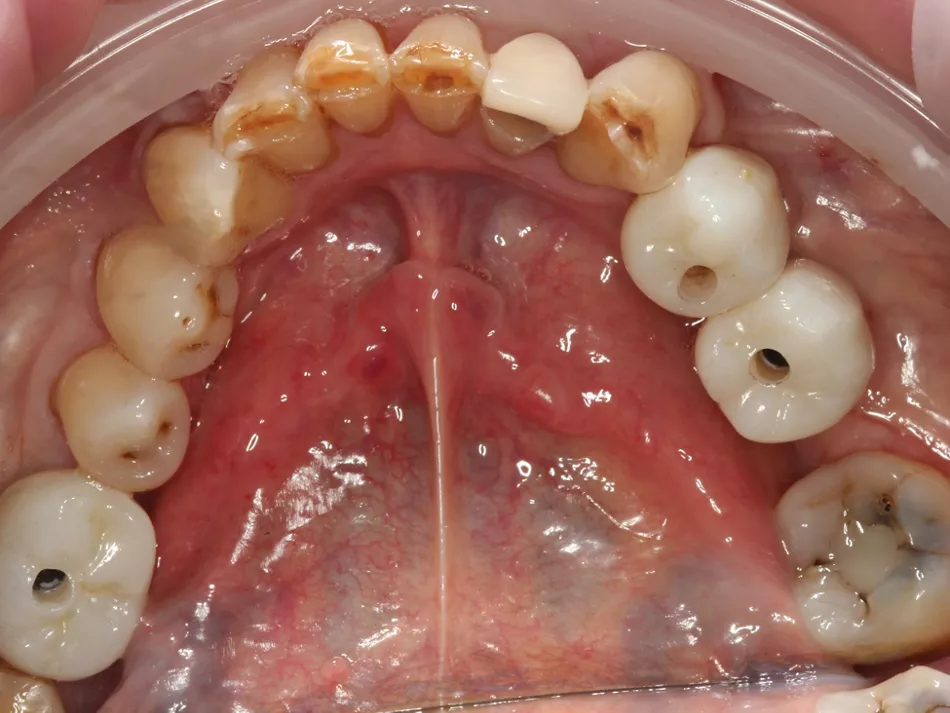

2a. 2b. Preoperative frontal and occlusal view of the lower arch showing multiple missing teeth.

2a

2b